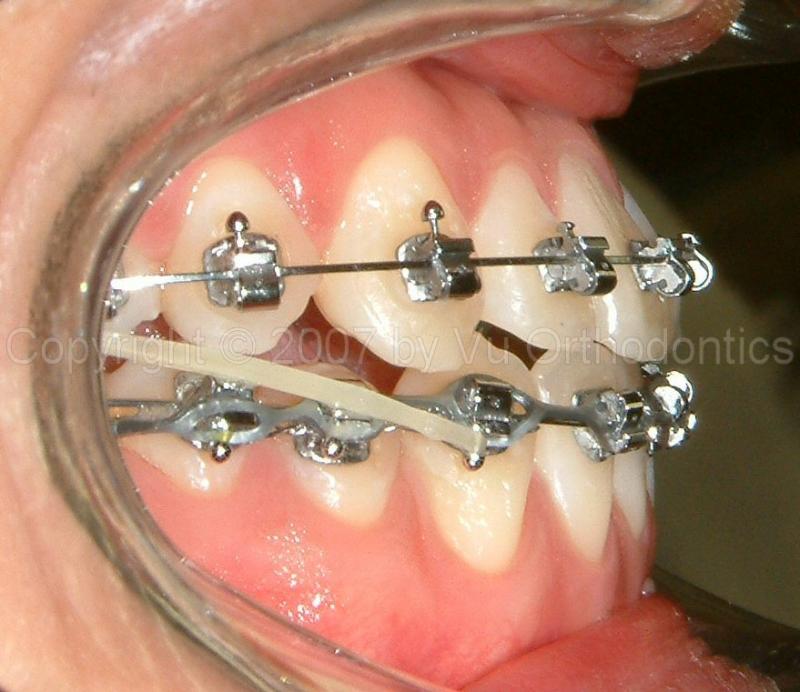

Case 5: 21 yr-old male

This case is skeletal Class III (moderate, with Class III malocclusion, with molars not shown); treated without orthognathic surgery and without extraction. Patient wanted no orthognathic surgery.

Fig. 11 View shows negative ovejet (initial): (a) Patient had braces elsewhere with treatment plan of orthognathic surgery, but he wanted no surgery; (b) After existing braces are removed.

Fig. 12 View shows progress (9 months): with Class III mechanics and no surgery